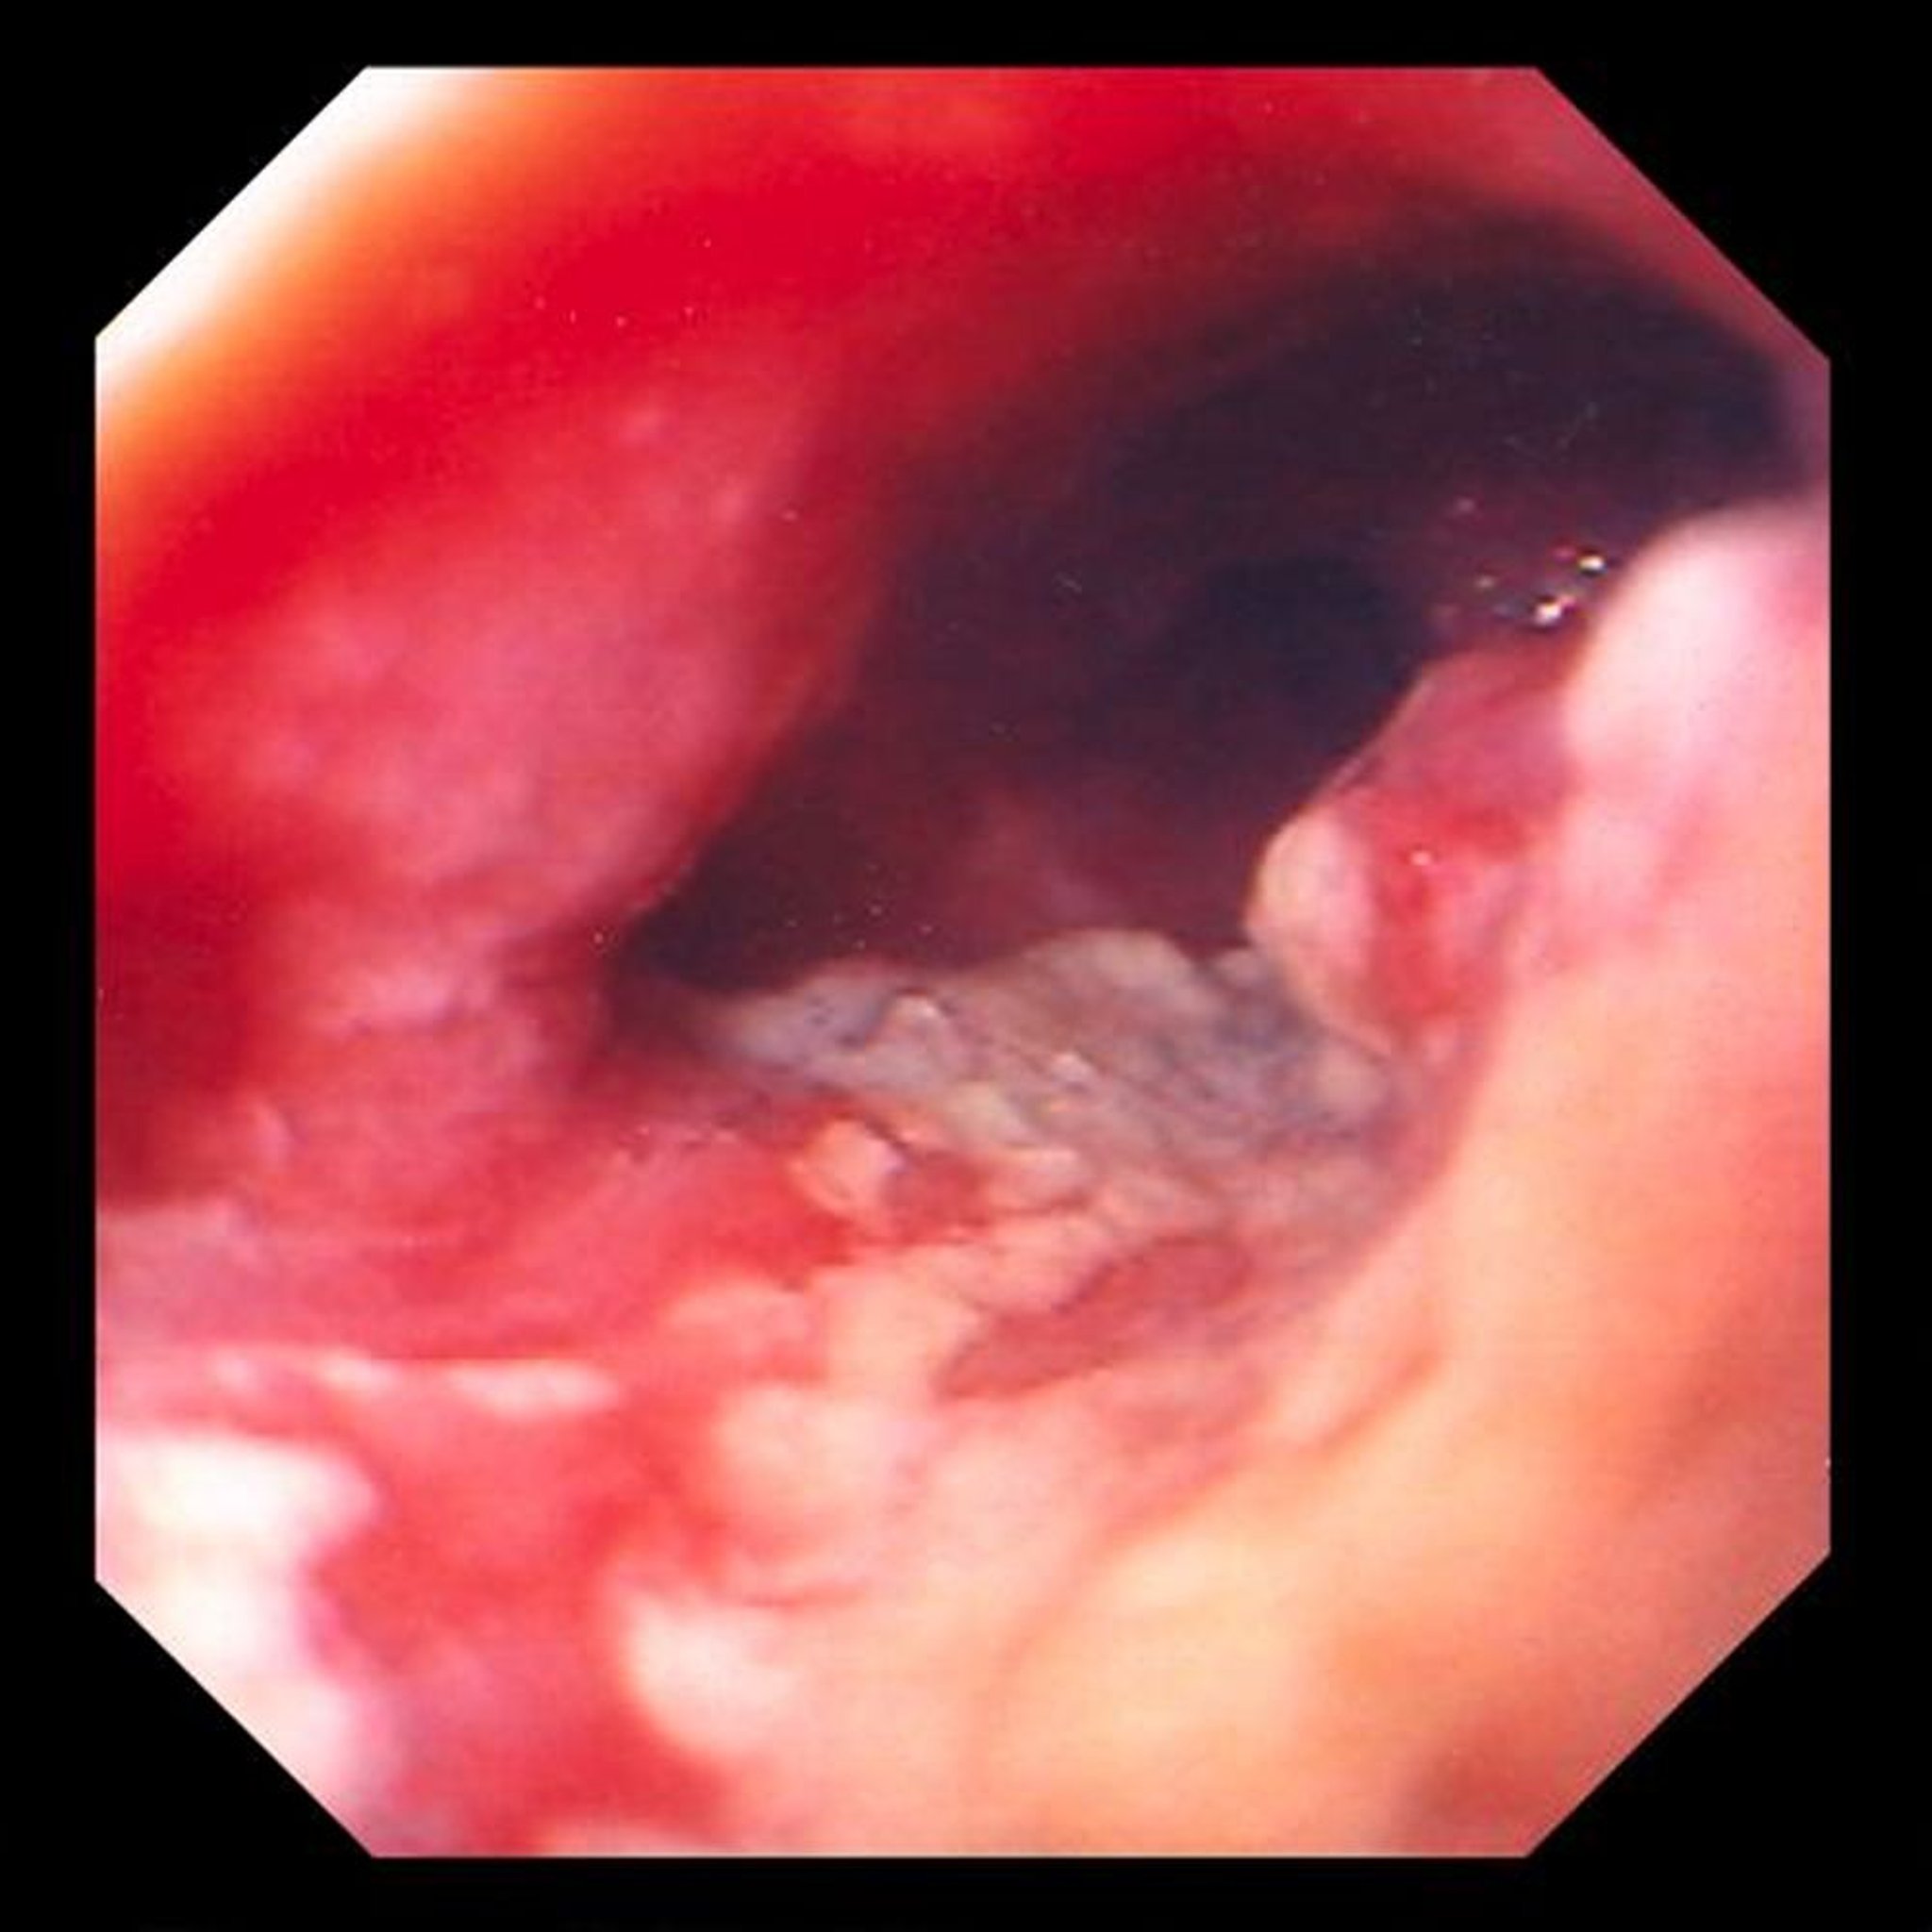

Ung thư biểu mô tuyến ở thực quản

Hình ảnh này cho thấy một khối u bị loét, co kéo nằm ở đầu xa thực quản, gợi ý cao đến ung thư biểu mô tuyến phát sinh từ những thay đổi chuyển sản biểu mô trụ (Barrett thực quản).

Hình ảnh do bác sĩ David M. Martin cung cấp.